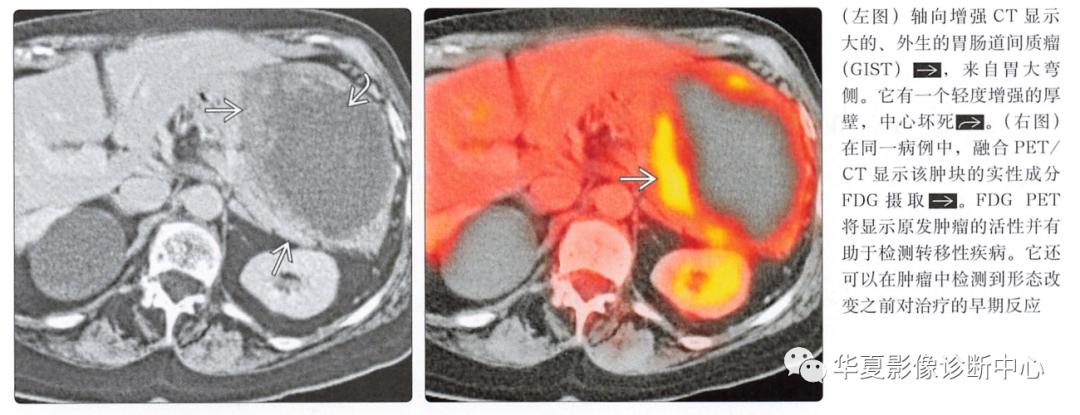

核医学表现

PET

预测对伊马替尼(格列卫)的早期反应优于CT

高代谢(FDG-摄取) 病灶提示存活肿瘤

原发性肿瘤和转移瘤均为高代谢

敏感性(86%),特异性(98%)

增强CT、PET